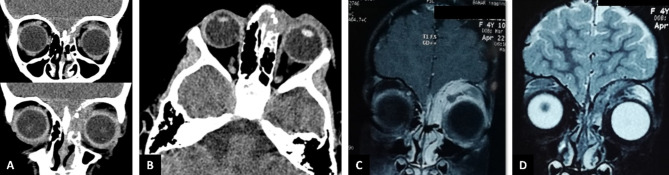

Case presentation: A 4-year-old female presented with an ill-defined, irregular, erythematous mass-like lesion measuring 8 × 10 mm on the left upper eyelid. Orbital computed tomography (CT) revealed an infiltrative soft tissue mass with bone erosions and destruction on the medial side of the frontal bone, extending toward the fronto-maxillary suture in the anterior orbit. Except for the left anterior ethmoidal sinus, the other paranasal sinuses were nearly clear. Magnetic resonance imaging (MRI) showed enhancement of the adjacent dura mater near the site of bony erosion and lesion expansion. The lesion was surgically excised, with drainage of mucopurulent discharge. Pathological examination revealed necrotizing granulomatous inflammation and fungal hyphae, with Aspergillus fumigatus growth confirmed by culture. The patient was diagnosed with invasive orbital aspergillosis. She was treated with intravenous and then oral voriconazole, and there was no recurrence of the disease.